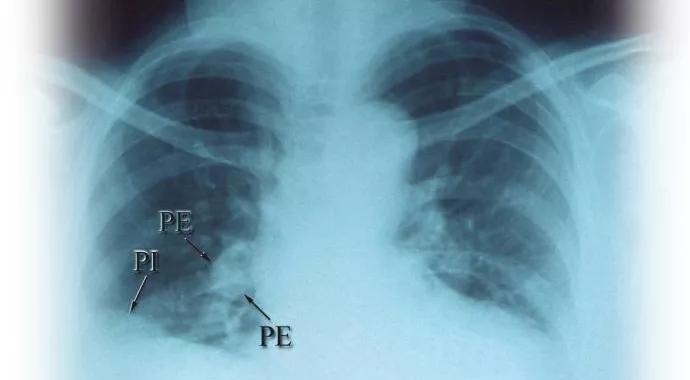

Although VTE should always be considered in a clinically suggestive setting, there is a higher association of these events with active disease. For this reason, we should be particularly watchful for any symptoms or signs that may suggest a VTE around the time of a new diagnosis or relapse of GPA/MPA/EGPA. These presentations can commonly include not only unilateral leg swelling but also bilateral leg swelling, as was seen in Case 1, as well as features that might suggest a pulmonary embolism.